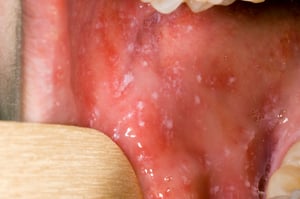

Les taches de Koplik de la muqueuse buccale ressemblent à des grains de sable blanc entourés d'aréoles rouges. Ces énanthèmes sont pathognomoniques et apparaissent chez 70% des patients (2). Les taches de Koplik apparaissent pendant le prodrome, avant le début de l'exanthème, généralement sur la muqueuse buccale, en regard des 1ères et 2e molaires supérieures. Elles peuvent être étendues, provoquant un érythème marbré diffus de la muqueuse buccale.

Les taches de Koplik sont classiquement décrites comme des taches rouge vif avec des centres blancs ou blanc bleuâtre qui peuvent ressembler à des grains de sable. Elles peuvent se former n'importe où dans la bouche, précèdent souvent l'exanthème généralisé et sont pathognomoniques de la rougeole.